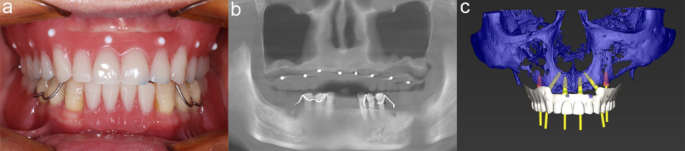

Preoperative design. (a) diagnostic denture (b) Preoperative cone beam computed tomography (CBCT) scan (c) Prosthetically guided implant design.

An alginate impression was taken to create a diagnostic model that captured the patient’s centric occlusion relationship using a wax bite. A diagnostic denture was then fabricated, featuring randomly distributed radiopaque points across its surface (Fig. 1a). Following this, a cone beam computed tomography (CBCT) scan was conducted (Fig. 1b). Separate digital scans of both the patient’s diagnostic model and the denture were obtained. The digital scan data were integrated with the CBCT data using CoDiagnostiX Version 9.11 software (Straumann, Switzerland) to generate a comprehensive digital model encompassing the bone structure, soft tissues, and virtual prosthesis.

To facilitate prosthetically guided implant placement, implants were accurately designed, and digital guides were created (Fig. 1c). Two implants were planned for zones 1, 2, and 3. Additionally, an immediate short arch restoration with four implants was designed for zones 1 and 2, as there was insufficient bone volume in zone 3 to achieve initial stability during implant placement15.